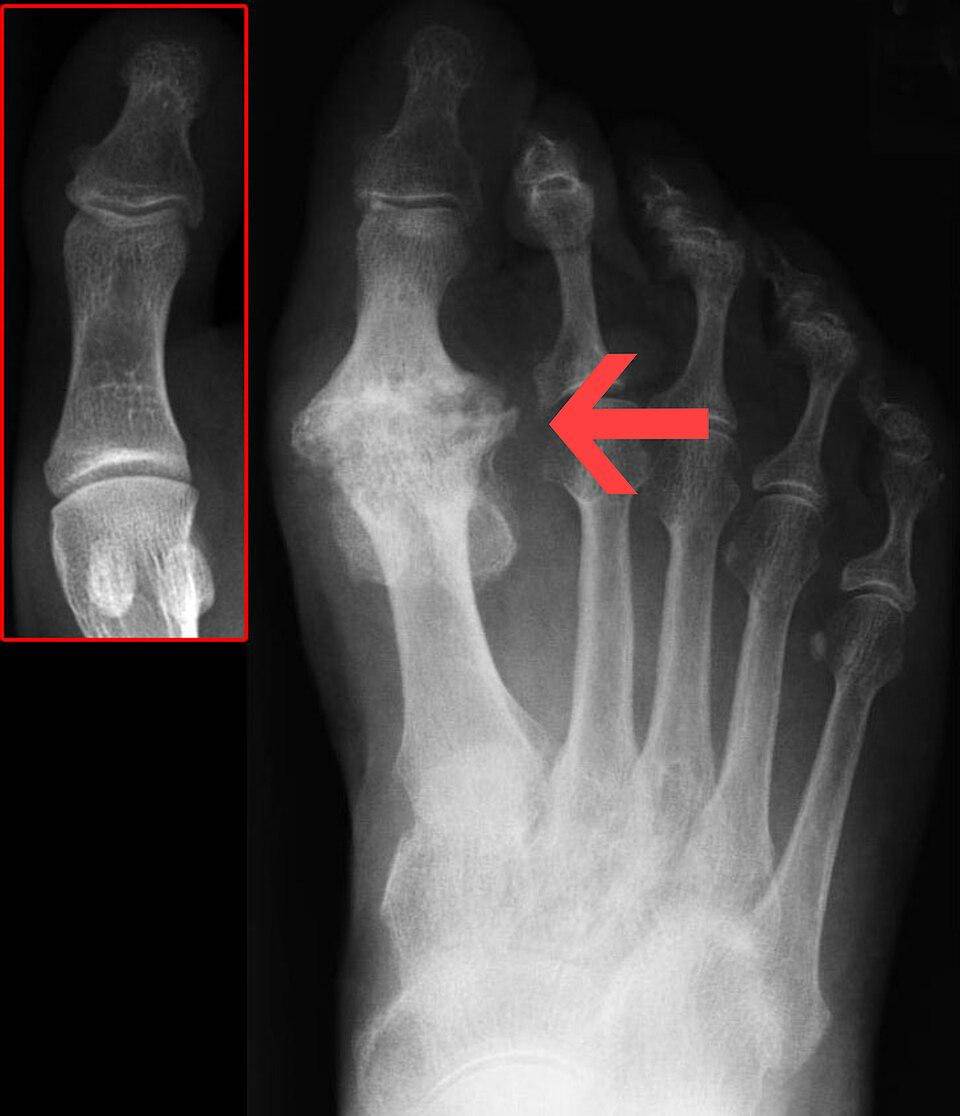

3. Metatarsalgia

Metatarsalgia adalah nyeri pada bola kaki tempat lima tulang metatarsal berada. Metatarsal membantu membentuk lengkungan kaki, yang penting untuk aktivitas berjalan dan menahan beban.

Nyeri metatarsalgia sering digambarkan sebagai nyeri yang tajam atau terbakar. Kondisi ini bisa memburuk saat kamu berdiri, berlari, berjalan, atau melenturkan kaki.

Metatarsalgia paling sering dialami orang yang sering berlari atau melompat. Faktor risiko metatarsalgia lainnya meliputi:

Pelari dapat mengalami artritis pada sendi mana pun di kaki, tetapi artritis ini sangat umum terjadi di sepanjang kepala dan pangkal tulang metatarsal. Karena artritis terjadi akibat degenerasi akibat akumulasi keausan, pelari yang lebih tua lebih rentan terhadap artritis.

Artritis di kaki adalah kondisi kronis yang berkembang perlahan seiring waktu. Kondisi ini jarang terjadi secara tiba-tiba kecuali terjadi cedera traumatis (seperti fraktur Lisfranc).

9. Hallux rigidus

Hallux rigidus, atau jempol kaki kaku, adalah bentuk artritis degeneratif yang dapat menyebabkan ketidaknyamanan yang signifikan.

Kondisi ini terutama memengaruhi sendi metatarsophalangeal, yang menghubungkan jempol kaki dengan bagian kaki lainnya.

Sendi ini sangat penting untuk berjalan dan berlari, dan penggunaan berlebihan atau cedera dapat mengakibatkan kondisi yang menyakitkan hallux rigidus.